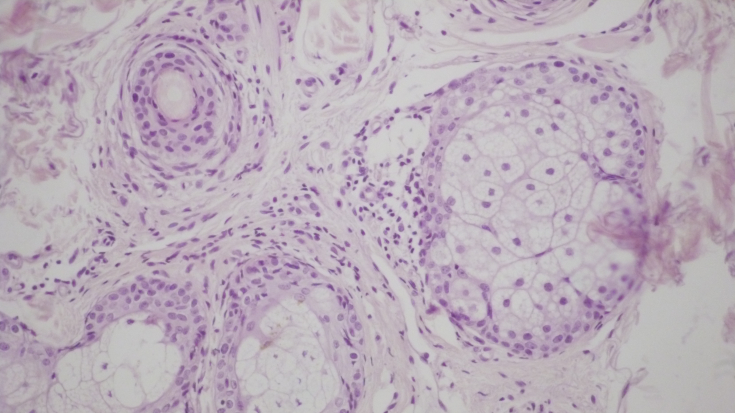

При контрольній гістологічній підготовці ділянки шкіри перед проведенням лікувальних заходів відзначалася вогнищева, значно виражена запальна інфільтрація в дермі у вигляді очагових скопінь лімфоцитів та гістіоцитів. (Рис. 1а, b). Проліферація дрібних судин капілярного та синусоїдного типу супроводжувалася периваскулярною лімфоїдно-клітинною інфільтрацією (мал. 1c). Навколо окремих волосяних фолікулів та сальних залоз запальна інфільтрація стимулювала проліферацію фібробластів та розвиток склеротичних процесів. (Рис. 1d).

Малий. 1. Морфологічна картина шкіри перед лікувальними заходами: вогнищева запальна інфільтрація дермі, х200; запальна інфільтрація навколо волосяних фолікулів, ознаки фіброзу, х200; проліферація дрібних сосудів капілярного типу з периваскулярною лімфоїдно-клітинною інфільтрацією, х200; сальні залози з вогнищевою запальною інфільтрацією у прилягаючій дермі, х200.